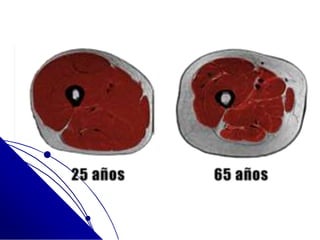

SARCOPENIA

 Raíz Griega:

 “sarco” = carne, músculo

 “penia” = deficiencia,

disminución

 Definición:

 Síndrome Caracterizado por

la Pérdida progresiva y

gradual de

 Masa, fuerza y funcionalidad

del músculo esquelético

 Relacionada con el proceso del

envejecimiento

 Que contribuye al daño y a la

dependencia funcional

SARCOPENIA  RaízGriega:  “sarco” = carne, músculo  “penia” = deficiencia, disminución  Definición:  Síndrome Caracterizado por la Pérdida progresiva y gradual de  Masa, fuerza y funcionalidad del músculo esquelético  Relacionada con el proceso del envejecimiento  Que contribuye al daño y a la dependencia funcional